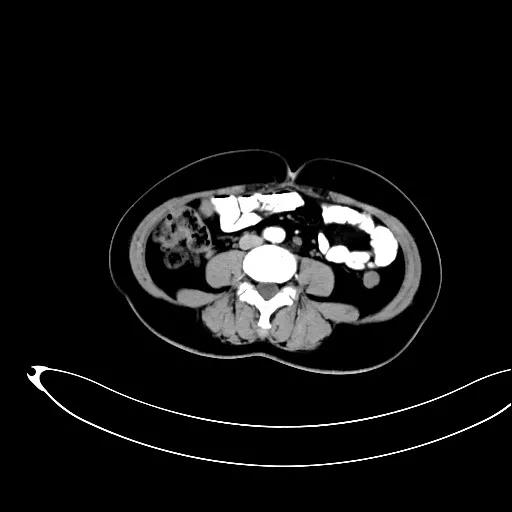

某患者因为“腹痛1周”而入院,外院B超提示子宫上方囊实性肿物,CT提示:左侧附件区占位,并盆腔及腹主动脉旁淋巴结转移。右肾动脉有右肾动脉及异位右肾动脉,其下均有肿大淋巴结。

排除禁忌后,在全麻下行“次广泛子宫切除+双附件切除+大网膜切除+阑尾切除术+盆腔淋巴结及腹主动脉旁淋巴结切除术”。术中切除腹主动脉左旁、右旁及后方淋巴结,达左右肾动静脉水平。多个淋巴结呈融合状态,长径约3-5cm。手术由陈亮副主任医师和宋趣清主治医师完成。

妇科一病区严格遵循指南推荐,在影像学或探查淋巴结阳性的晚期卵巢癌中,若能达到满意减瘤,仍常规行盆腔及腹主动脉旁肿大淋巴结切除/清扫术(如下图举例)。通过前期初步统计分析,肠系膜下动脉至肾静脉下淋巴结转移阳性率为25%左右,在全部腹主动脉旁淋巴结转移患者中约占30%,显示了肾静脉下腹主动脉旁淋巴结清扫的价值。其对生存的影响有待进一步观察。